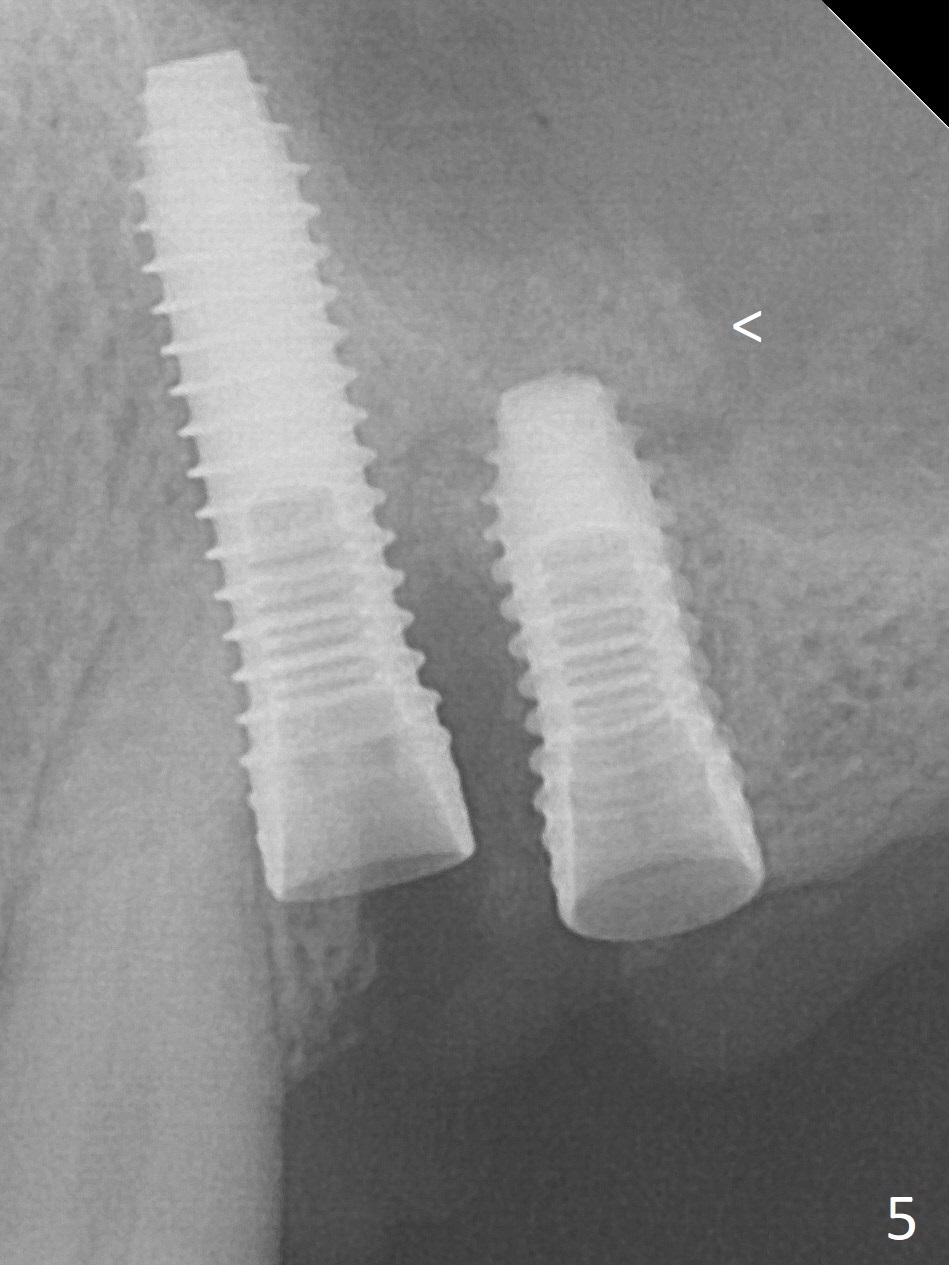

The buccal gingiva at #12 with vertical root fracture looks unhealthy (Fig.1). Osteotomy at #13 is initiated prior to #12 extraction. In fact the osteotomy happens in the extensive defect associated with #12 (Fig.2 red dashed line). To obtain primary stability, the osteotomy at #12 needs to be long, while that at #13 needs two-pointed fixation (Fig.3 *). After adjustment of trajectory at #12 and increase in diameter of the osteotomy at #13 (Fig.4), a 3.8x15 and 3.8x10 mm implants are placed (Fig.5). Following adjustment of implant depth (Fig.6), the implant at #12 becomes loose, while that at #13 tightens. With placement of abutments, an immediate splinted provisional is locked in place to stabilize the loose implant at #12 (Fig.7). The patient complains of cold sensitivity in the upper left quadrant, possibly related to the fact that the implant at #12 is close to the apex of the tooth #11. The position and trajectory of the initial osteotomies should be changed as shown in Fig.8 (white lines, as compared to Fig.2). There is no sensitivity 1 month postop. Impression is taken 4 months postop (Fig.9) after #13 mesiobuccal margin prep. The implants were placed too close to each other. The abutment screw at #13 is retightened 8 months post cementation. There appears no bone loss 9 months post cementation (Fig.10), while the tooth #11 has periapical infection with DL caries 1 year 7 months post cementation (Fig.11).